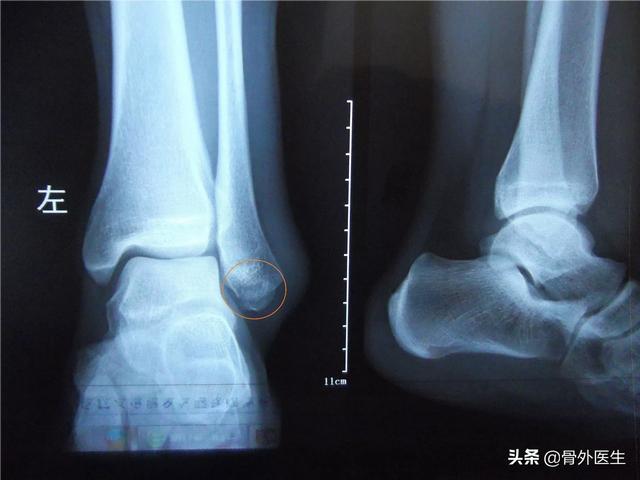

②内外踝牵拉性骨折 踝关节扭伤可以造成内外踝牵拉骨折,比如脚内旋,可以造成外踝牵拉性骨折,反之造成内踝骨折,那就要正规治疗,保守治疗或手术治疗。